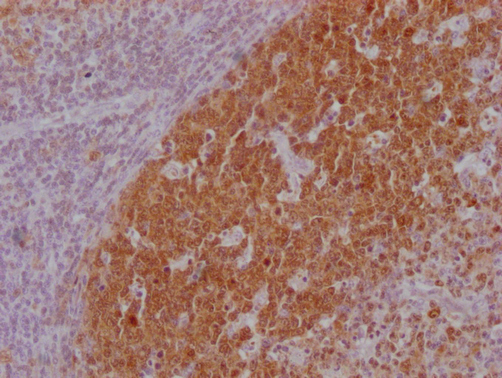

IHC image of CSB-MA181399 diluted at 1:100 and staining in paraffin-embedded human tonsil tissue performed on a Leica BondTM system. After dewaxing and hydration, antigen retrieval was mediated by high pressure in a citrate buffer (pH 6.0). Section was blocked with 10% normal goat serum 30min at RT. Then primary antibody (1% BSA) was incubated at 4°C overnight. The primary is detected by a Goat anti-mouse IgG polymer labeled by HRP and visualized using 0.05% DAB.

IHC image of CSB-MA181399 diluted at 1:100 and staining in paraffin-embedded human lymph node tissue performed on a Leica BondTM system. After dewaxing and hydration, antigen retrieval was mediated by high pressure in a citrate buffer (pH 6.0). Section was blocked with 10% normal goat serum 30min at RT. Then primary antibody (1% BSA) was incubated at 4°C overnight. The primary is detected by a Goat anti-mouse IgG polymer labeled by HRP and visualized using 0.05% DAB.